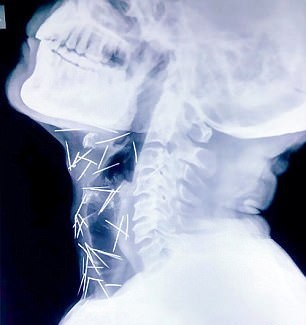

مردی با 75 عدد سوزن در بدن خود! + تصاویر

مردی هندی که برای انجام عمل جراحی‌ای ساده راهی بیمارستان شده بود پس از انجام رادیوگرافی، پزشکان متوجه وجود 75 سوزن در بدن این مرد شدند.

این مرد که «بادریلال مینا» نام دارد و در ایالت راجستان زندگی می‌کند برای عمل جراحی روی انگشت پایش به بیمارستان مراجعه کرد و پزشکان دریافتند سوزن های زیادی در پای او وجود دارد. بررسی‌های بیشتر نشان داد سوزن های دیگری نیز در بدن این مرد 56 ساله وجود دارد.

با اینکه این بیمار و خانواده‌اش از وجود این سوزن‌ها اظهار بی‌اطلاعی می‌کنند، به وضوح مشخص است آنها آگاهانه وارد بدنش شده‌اند.

تاکنون هیچکدام از بیمارستان‌هایی که این خانواده به آنها مراجعه کرده‌اند حاضر نشده‌اند برای خارج کردن این سوزن‌ها از بدن او کاری انجام دهند. از این 70 سوزن، 40 عدد از آنها در گلو، 25 عدد در پای راست و 2 عدد نیز در دو دست او است.

پسر این مرد می‌گوید از وجود این سوزن ها در بدن پدرش مطلع نبوده‌اند و فقط به دلیل احساس دردی که در پایش داشته او را به بیمارستان آورده‌اند و پس از آن به وجود سوزن‌ها پی برده‌اند.